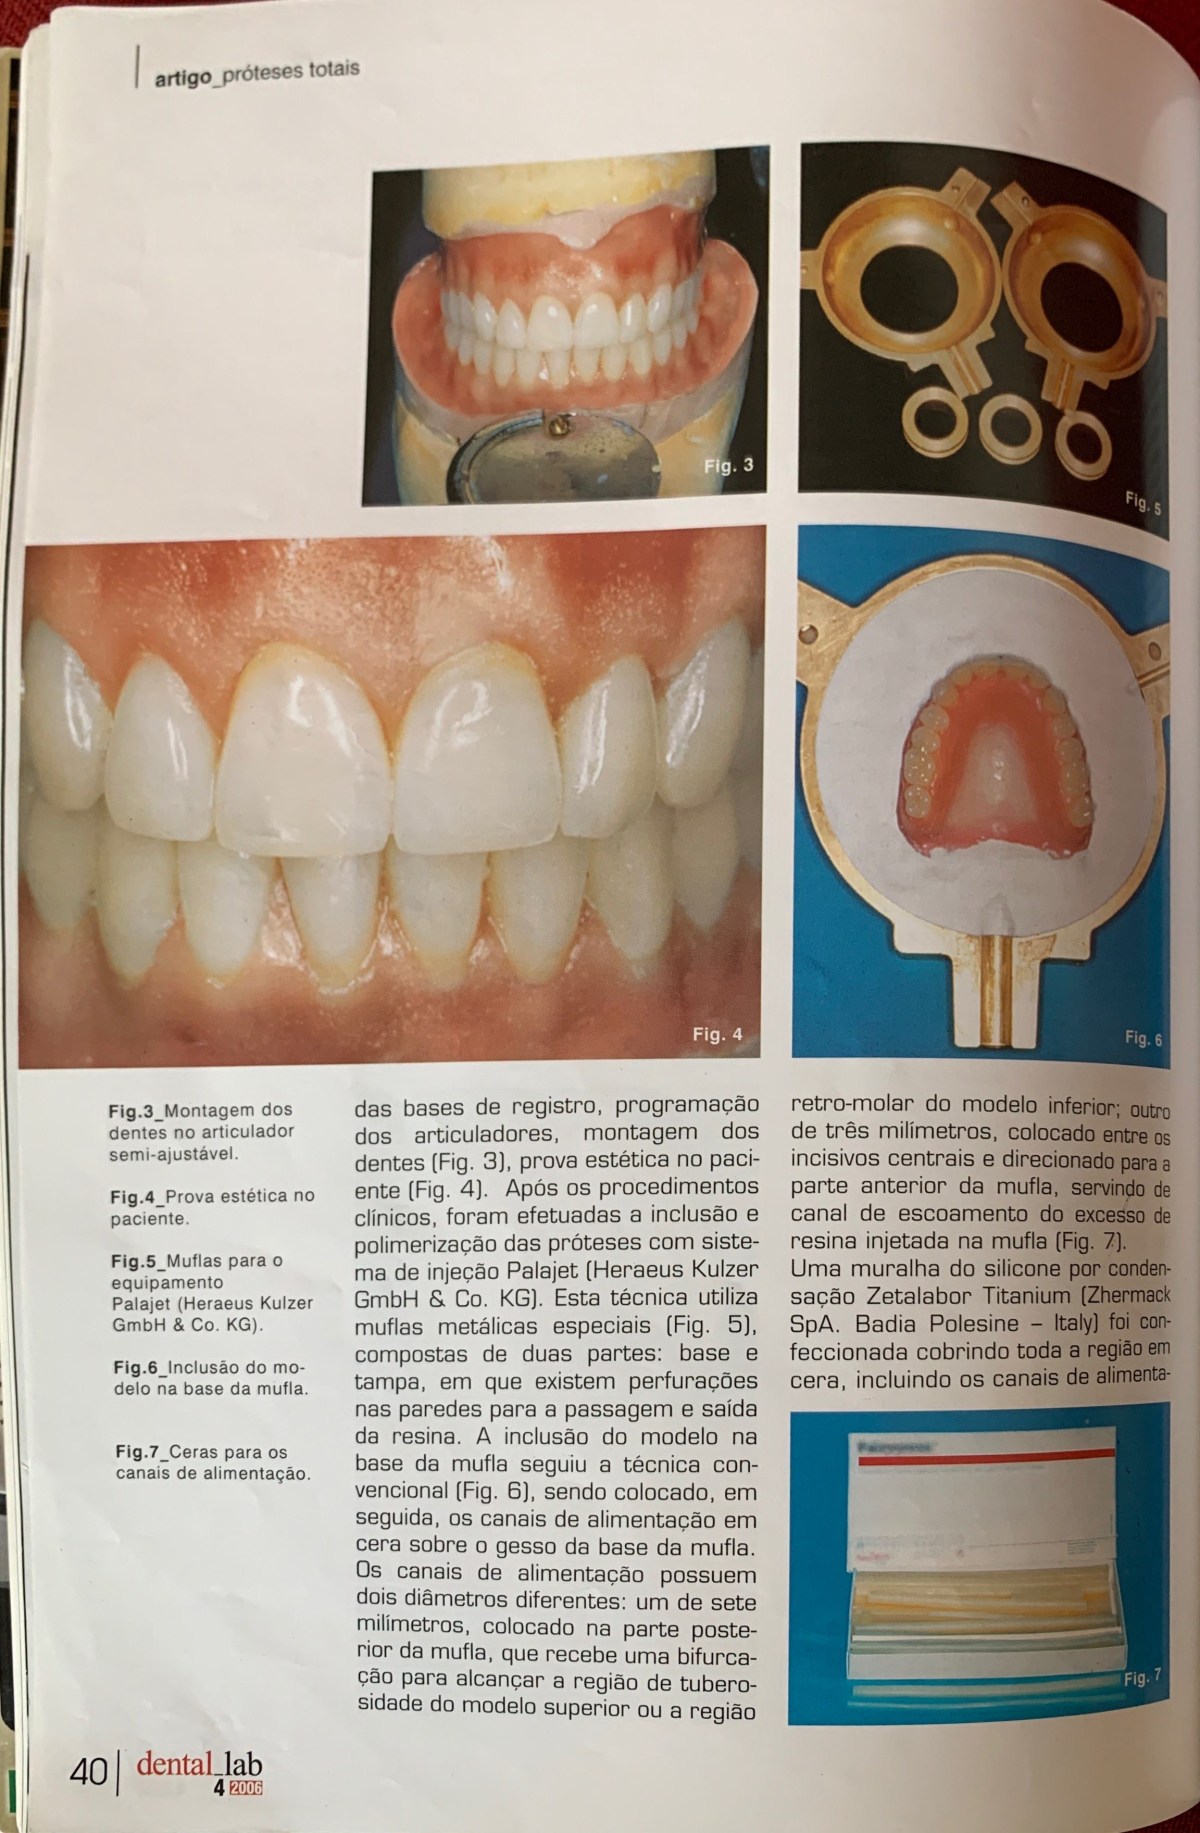

Sistema de Injeção no Processamento de Próteses Totais _relato de um caso clinico

Sistema de Injeção no Processamento de Próteses Totais _relato de…